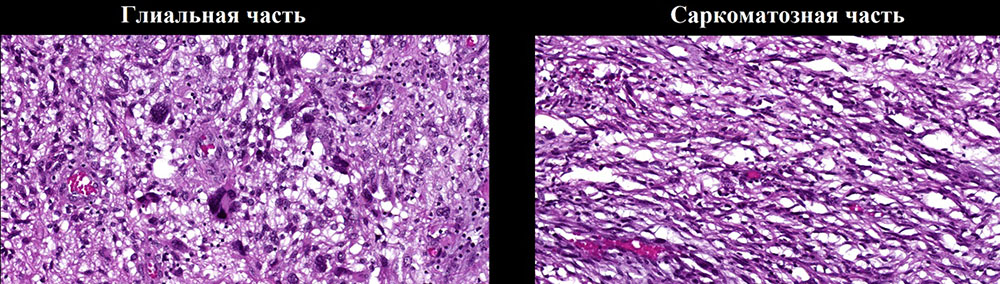

Глиосаркома  (послеоперационный препарат), окраска гематоксилином и эозином, увеличение х10. Глиальная часть демонстрирует выраженный ядерный полиморфизм и клеточную атипию. Саркоматозная часть представлена веретеновидной формы клетками с ретикулиновыми волокнами (соединительная (мезенхимальная) ткань).